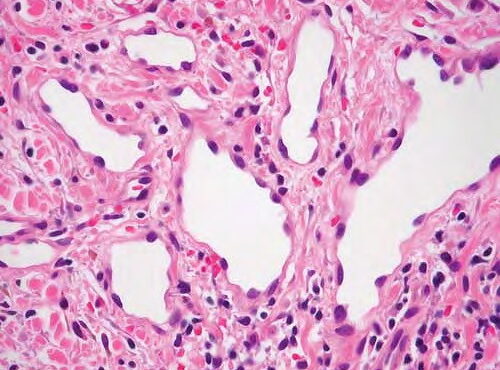

Targetoid hemosiderotic hemangioma =وعاؤوم دموي هيموسيدريني هدفي الشكل